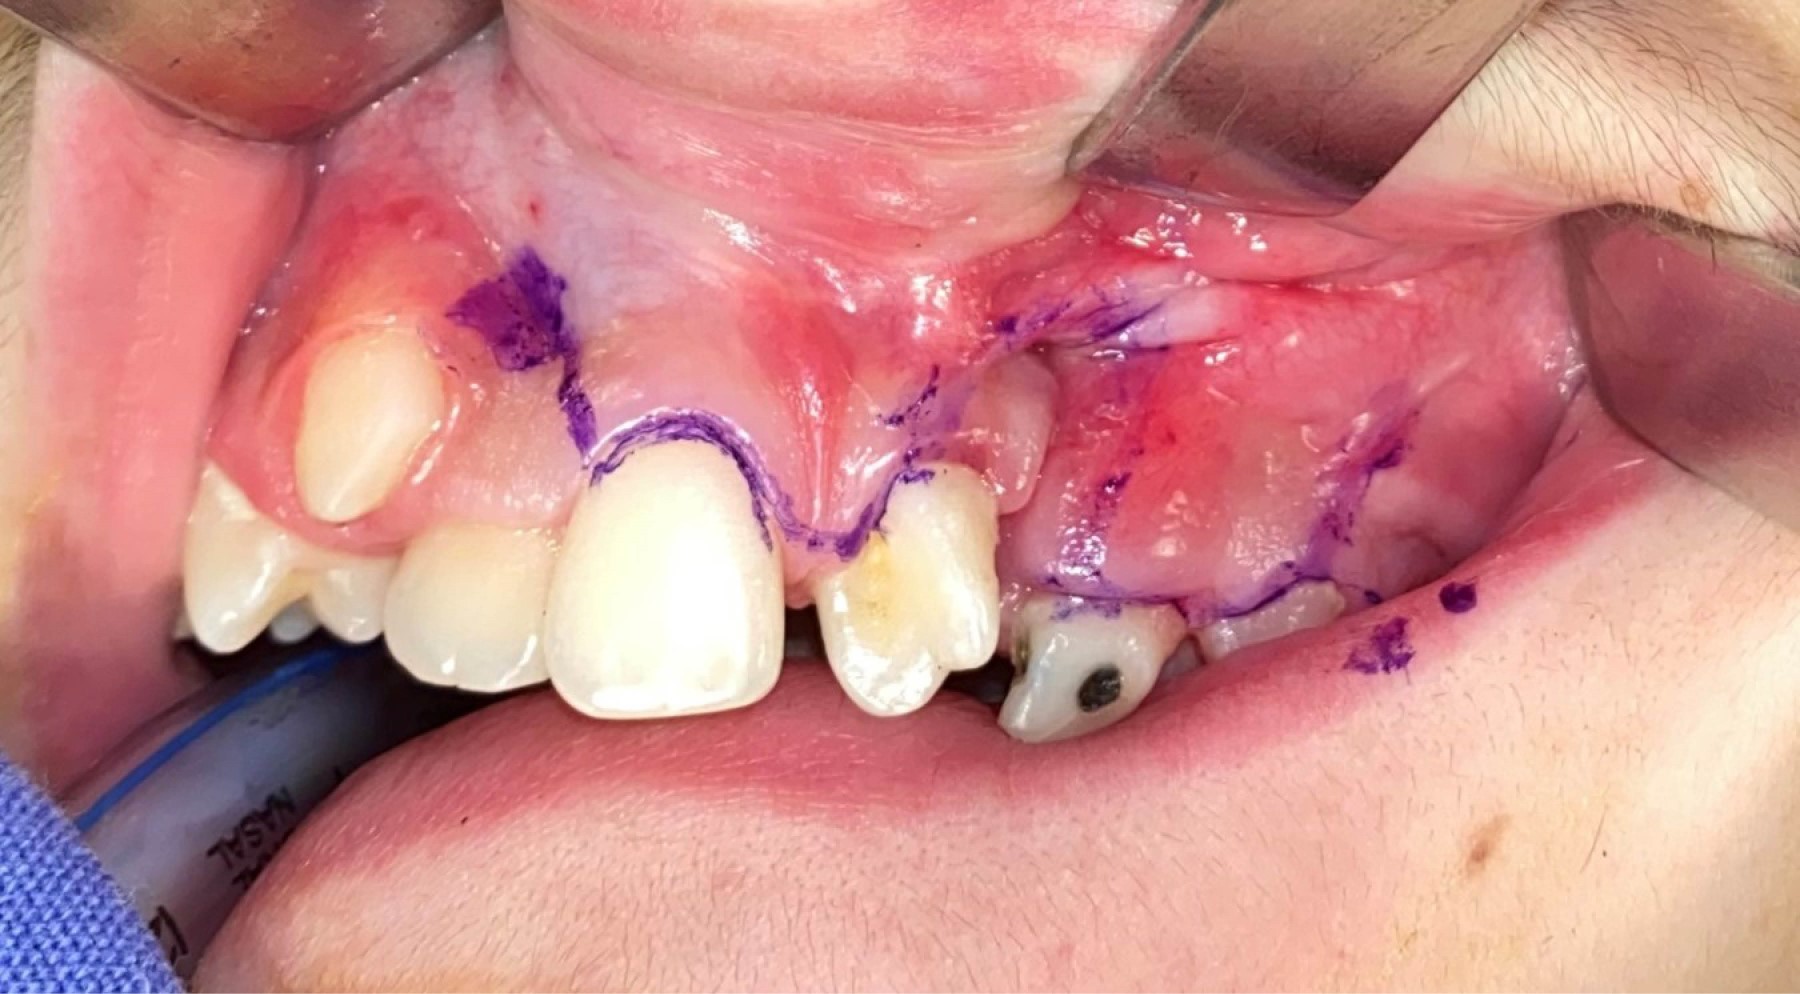

Use of plasma rich in growth factors with anterior iliac crest graft for repair of nasoalveolar cleft in patient with unilateral cleft lip and palate

Gómez-Hernández KA, Alonso-Moctezuma A, Castilla-Canseco H, Cuen-Lara E

Introduction: nasoalveolar fissures are common in patients with cleft lip and palate. Surgical treatment continues to feel the autologous bone graft with anterior iliac crest, however, the main complication of the surgical site is bone exposure and graft loss. Objective: the objective of this clinical case is to show how the use of biomaterials such as plasma rich in growth factors allows to improve the integration of the bone graft by avoiding the dehiscence of the gum. Case presentation: we present a 36-year-old female patient with cleft lip palate and nasoalveolar fissure treated by bone graft of nasoalveolar fissure and plasma rich in growth factors, presents adequate integration of the graft and scarring of soft tissue at six and 12 months postoperatively. Conclusions: the use of biomaterials such as plasma rich in growth factors is suggested to avoid dehiscence and graft compromise, thus avoiding a second surgery.

Figure 1